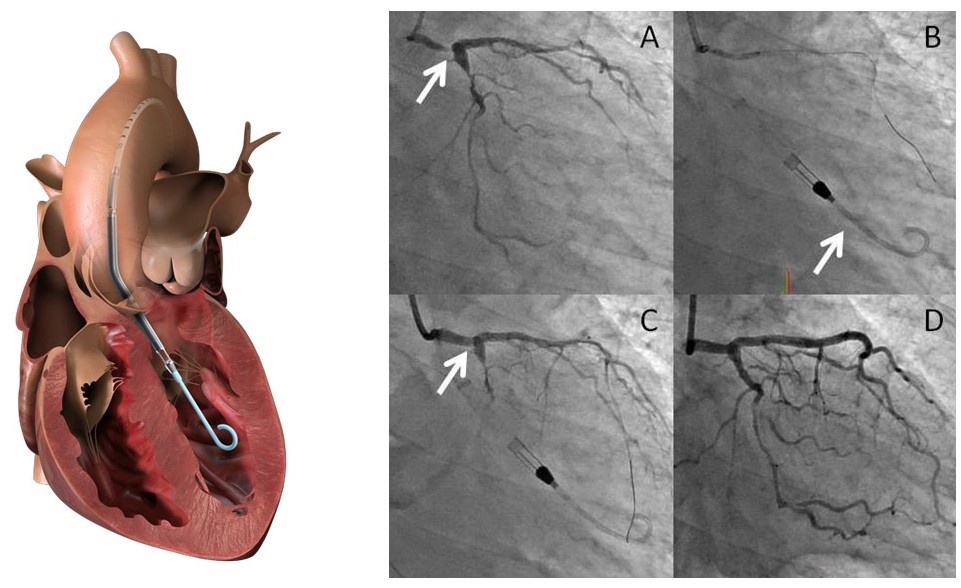

インペラ(補助循環用ポンプカテーテル)

インペラは左心室に留置するカテーテルで,左心室から血液をくみ上げ,カテーテルの内腔を通して左心室を出たところ(上行大動脈)に血液を放出させるポンプです.PCPS((経皮的心肺補助装置)では,全身循環は維持できるものの,心臓への負荷を取ることはできません.インペラは左心室の負荷を減らし,かつ,全身循環を維持することが出来るため,心機能の改善にもつながります.インペラ使用例は,全例登録が義務付けられており,適正使用かどうかが監視されています.

当院は救命救急センターであり,重症患者,特に心原性ショックの患者さんが多数搬送されます.既存の治療では救命できなかった患者さんを救うべく,この度インペラの導入に至りました.厳しい施設基準の要件を満たし, 2021年6月にインペラ施設に認定され,同月から使用を開始致しました.千葉県で認定されているのは11施設(2024年2月時点)のみです.

インペラ使用により救命できた,左冠動脈主幹部の急性心筋梗塞の症例をお示しします.左冠動脈主幹部の高度狭窄病変(下図A)に対して,インペラ挿入により速やかに左心室の負荷をとり経皮的冠動脈インターベンション(PCI)を施行しました(下図B).左冠動脈主幹部は十分な拡張が得られました(下図C).後日待機的に残存病変にも治療を加え(下図D),無事に退院することが出来ました.